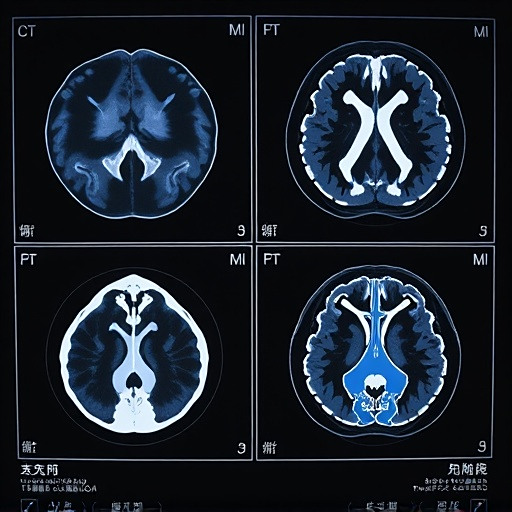

医学影像学包括哪些检查项目?X线、CT、MRI等检查有什么区别?

医学影像学 医学影像学是一门利用各种成像技术对人体进行无创检查的学科。它通过X射线、CT、MRI、超声等设备获取人体内部结构的图像,为临床诊断和治疗提供重要依据。 医学影像学的主要技术包括: X射线摄影是最基础的成像方式,适用于骨骼系统和胸部检查。CT扫描通过多角度X射线获取断层图像,对软组织分辨...